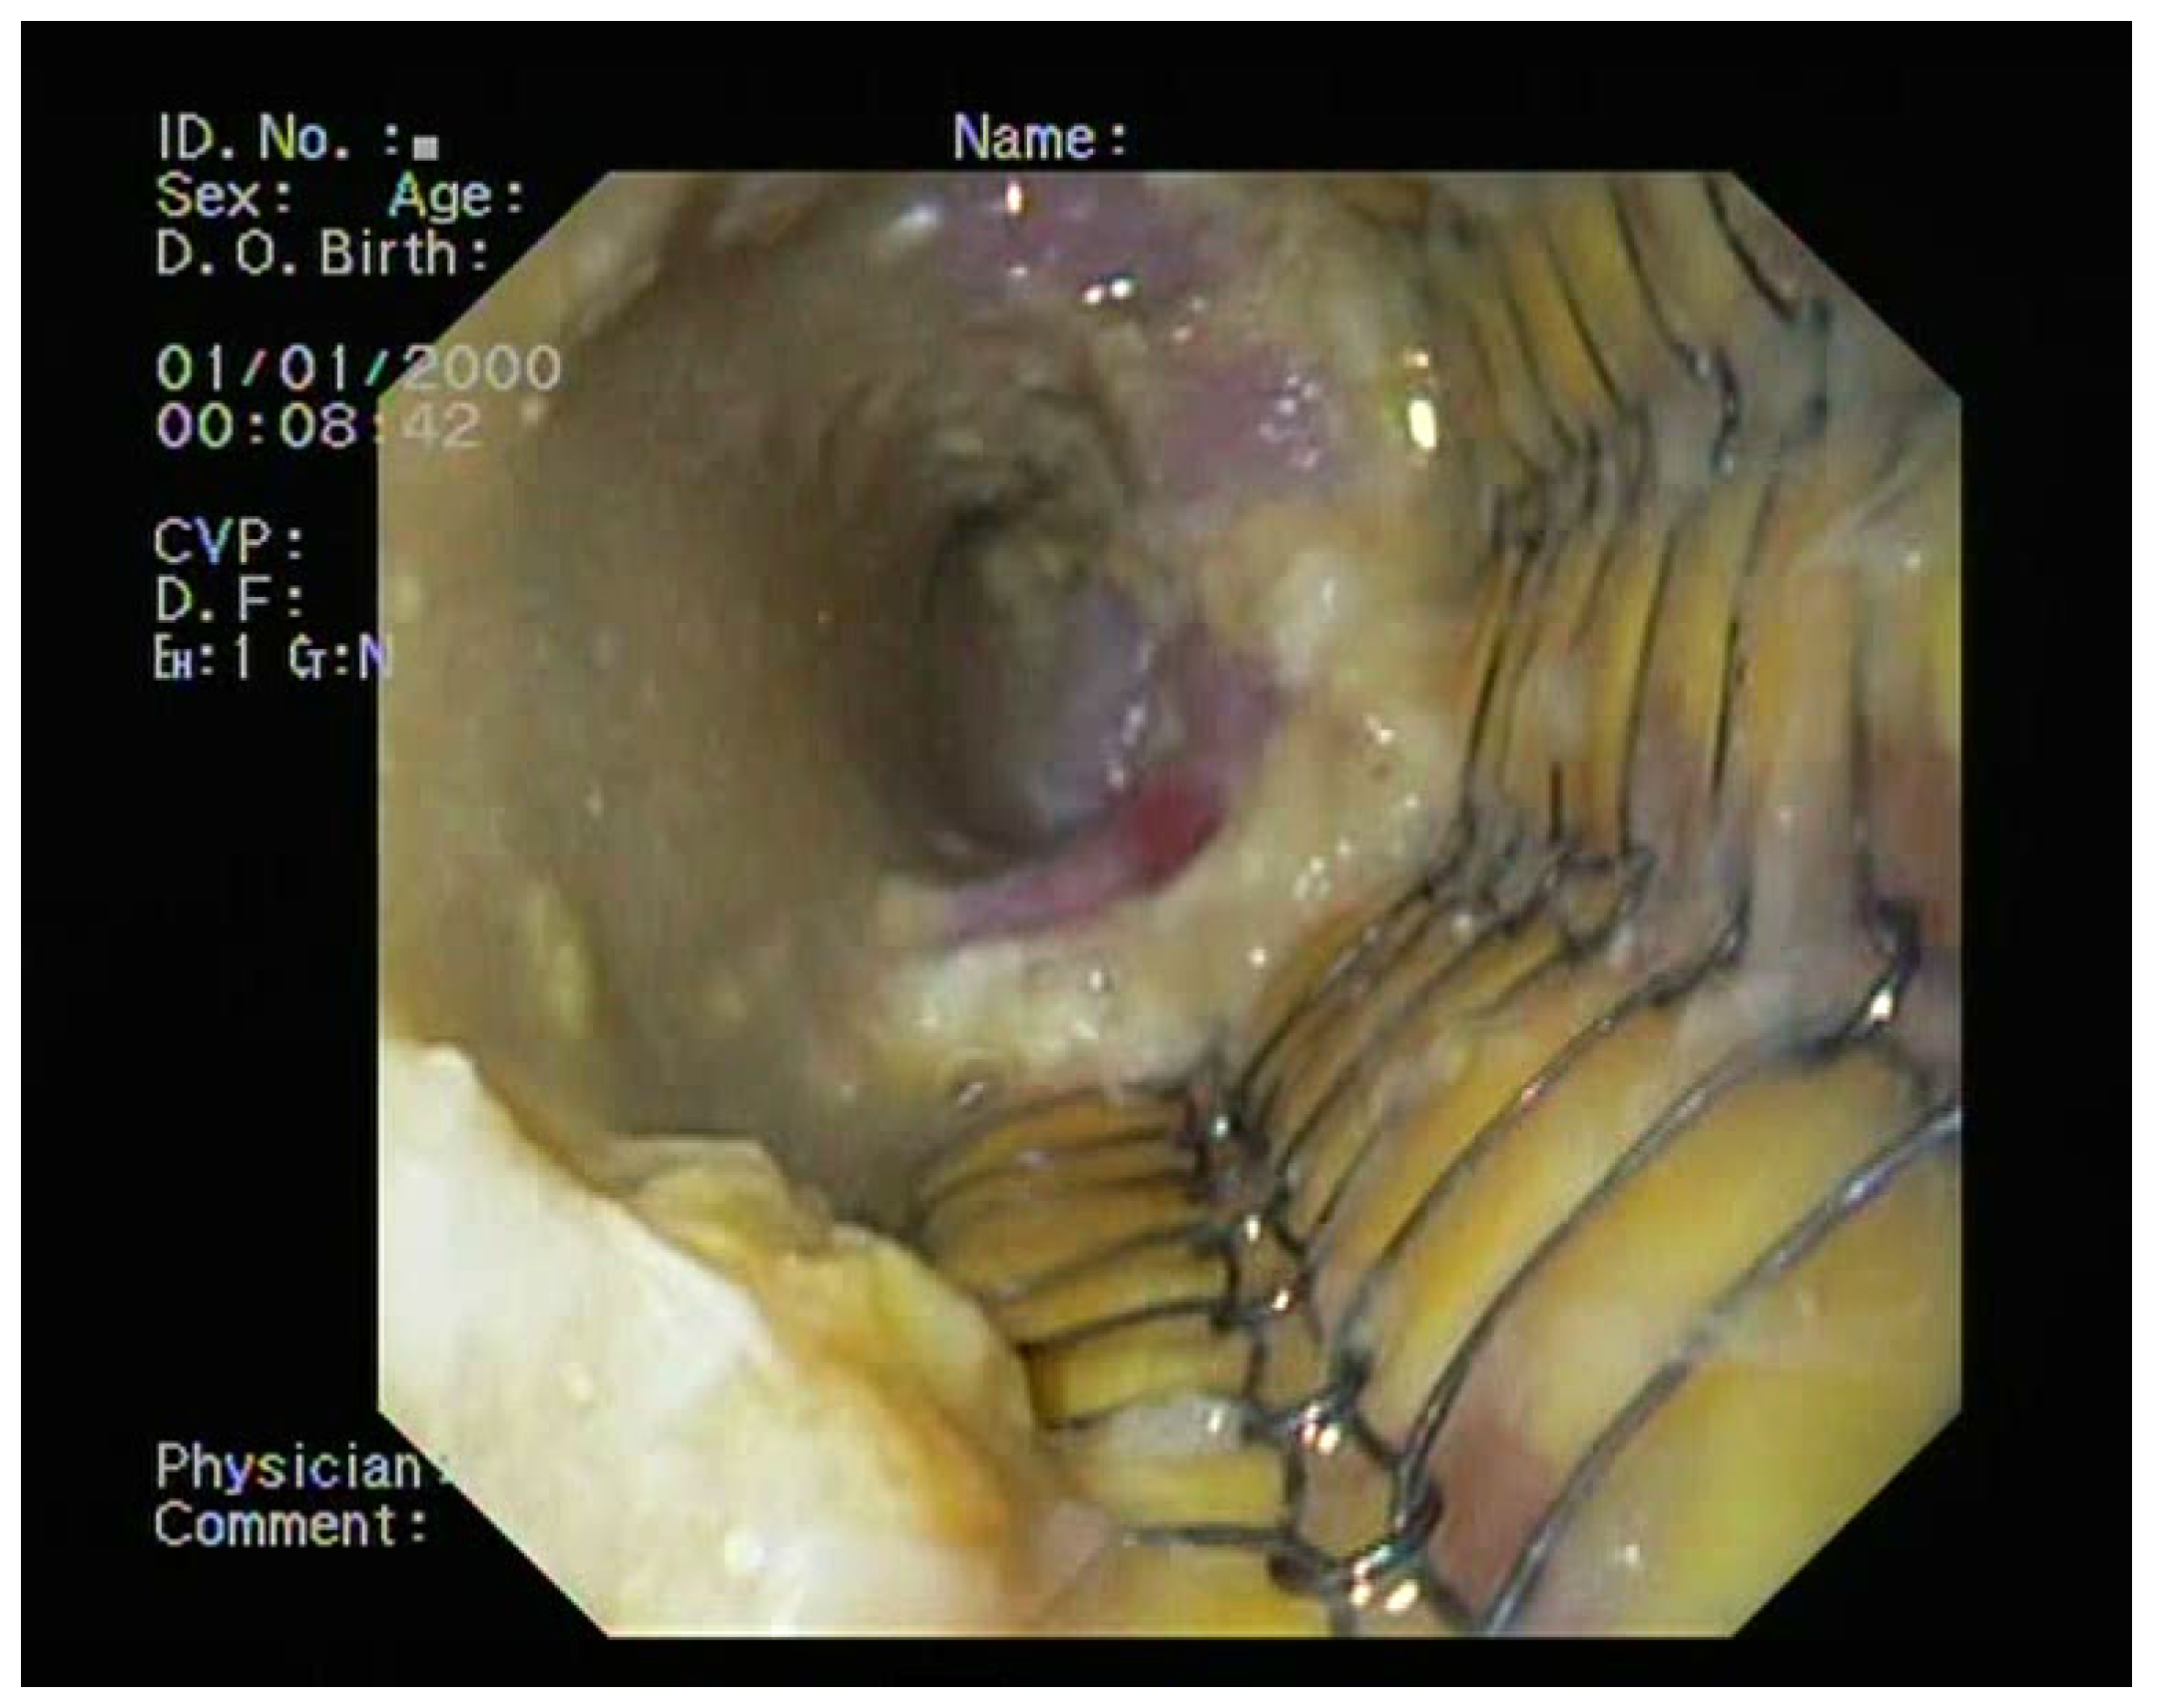

2.4. Treatment